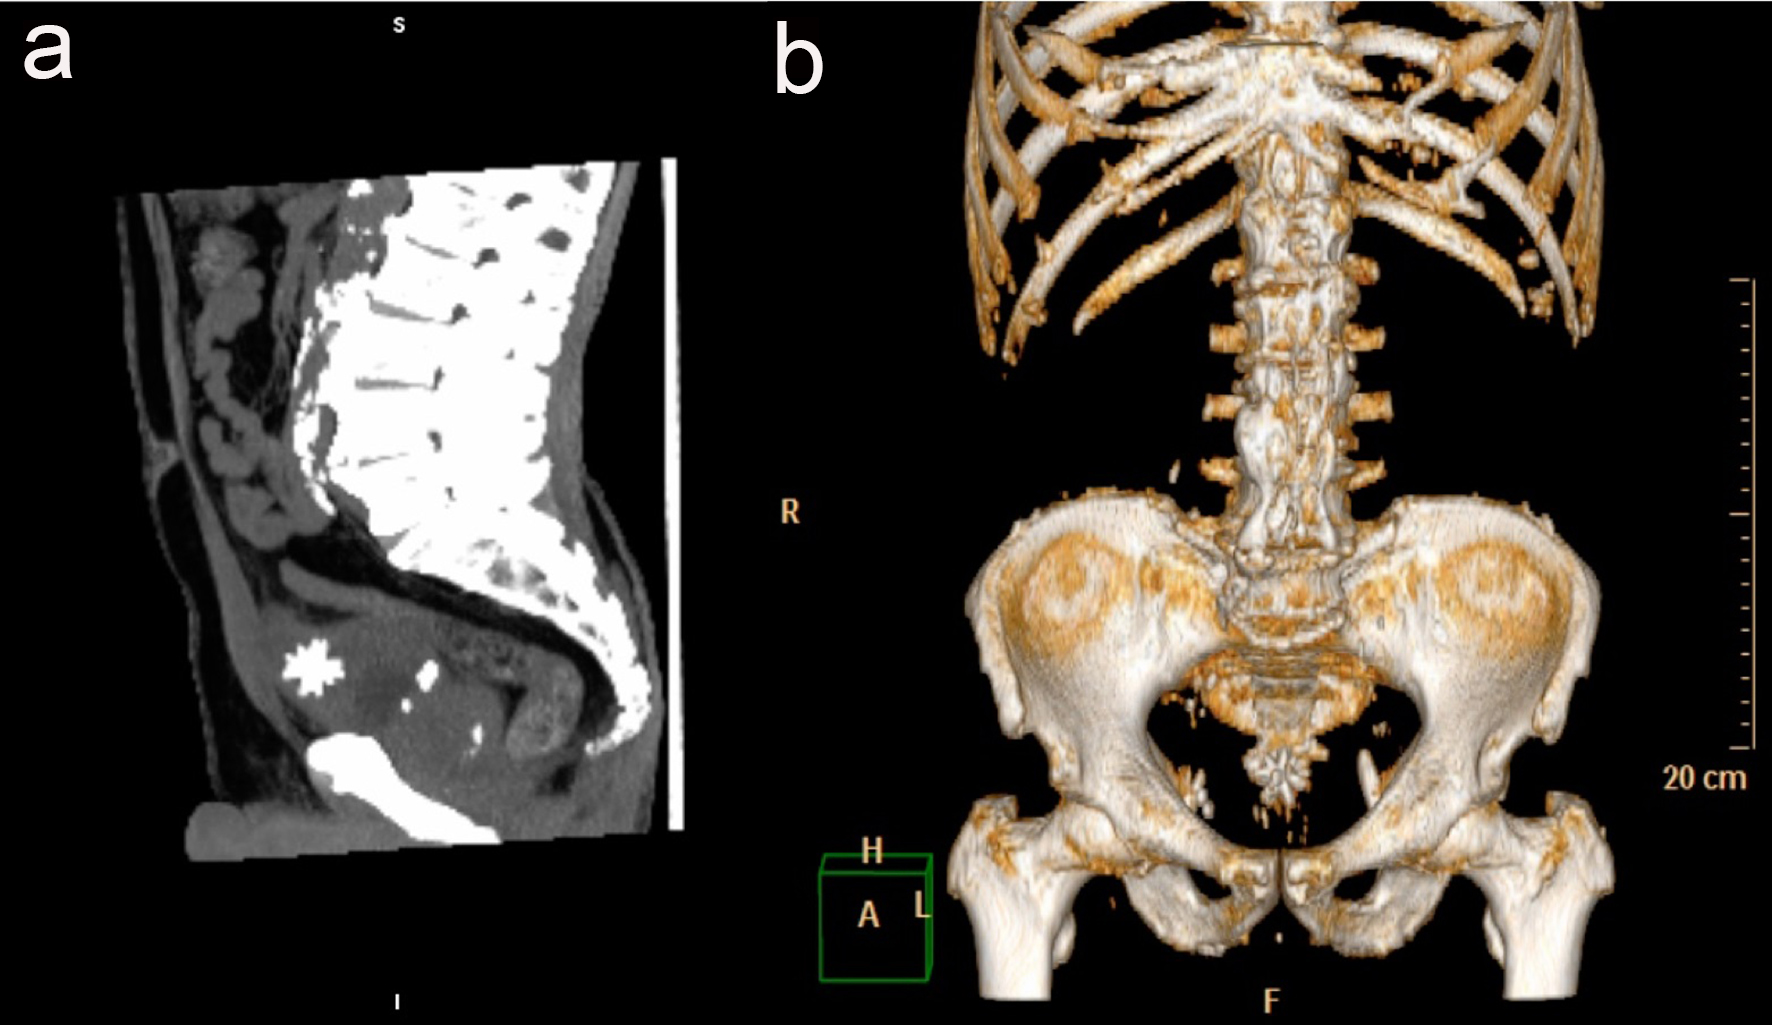

A 84-year-old man with cognitive impairment and non-specific abdominal pain came to our observation. Relatives stated that the man had suffered from benign prostatic hypertrophy for many years and that there was also a history of chronic renal failure and diverticulosis. A month earlier the patient had an episode of macroscopic hematuria. Hematological, microbiological and biochemistry examinations revealed no abnormalities, but confirmed only high creatinine levels. An abdominal computed tomography examination (CT) without contrast was also requested to rule out diverticulitis. The study was performed on a Philips Brilliance CT 16-slice scanner and was completed by multiplanar (MPR) (Fig. 1), 3D maximum intensity projection (MIP) and volume rendering (VR) reconstructions (Fig. 2). A stone of 3 × 2.4 × 3.2 cm with a central dense core and peripheral and speculated projections was visible in the poorly distended bladder. The appearance of the stone was compatible with a Jackstone calculus (Fig. 3). It was located between the bladder body and the dome (Fig. 1a, b). At this point, the bladder walls were also thickened (Fig. 1a). Other little stones with regular appearances were also visible at the part of the bladder base. The patient’s prostate was enlarged, measuring 5.7 × 5 × 5.3 cm (Fig. 1b).

![]() Click for large image | Figure 2. The Jackstone calculus on MIP 3D reconstruction on sagittal plane (a) and on VR (b). |